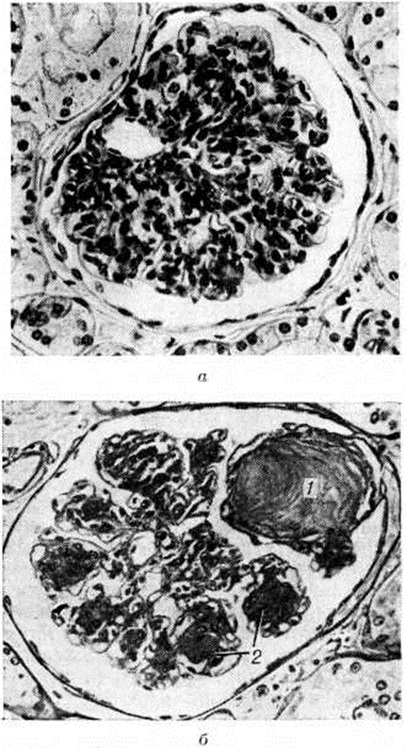

Гломерулосклероз диабетическийГломерулосклероз диабетический (латинское glomerulus клубочек + склероз; греческий diabetes, от diabainein проходить; синонимы: интеркапиллярный гломерулосклероз, синдром Киммелстила — Уилсона) — специфическая и наиболее частая форма поражения почек при сахарном диабете; впервые описана в 1936 году. Гломерулосклероз диабетический является одним из наиболее тяжёлых осложнений сахарного диабета (смотри полный свод знаний Диабет сахарный). Частота Гломерулосклероз диабетический по материалам аутопсии колеблется от 19,5% [Хендерсон (L. Henderson)] до 50,9% [Уайт (White)] у больных, страдающих сахарным диабетом свыше 20 лет. В клинике Гломерулосклероз диабетический, по данным Р. А. Хейфец и Л. И. Каминской, выявляется в 6%, по данным Э. Глоссит Москович — в 17,8% и даже в 48% случаев (В. В. Сура) от числа больных, страдающих сахарным диабетом. У женщин, страдающих сахарным диабетом, Гломерулосклероз диабетический встречается в 30%, у мужчин — в 19,5% случаев. Патологическая анатомияГистологические изменения почек при Гломерулосклероз диабетический весьма полиморфны; выделены три основных формы поражения — узелковая, диффузная и экссудативная. Некоторые авторы вместо экссудативной выделяют смешанную форму. Узелковая форма характеризуется наличием в клубочках эозинофильных образований (узелков) округлой или овальной формы (рисунок 1), содержащих вакуоли. Они могут занимать часть или весь клубочек, по периферии которого в последнем случае располагаются сохранившиеся сдавленные капиллярные петли. Одновременно наблюдается расширение и аневризмы капилляров клубочков, утолщение их базальных мембран. При гистохимическом исследовании узелков они вначале окрашиваются как фибрин, а в дальнейшем как коллаген. Узелки содержат большое количество высокомолекулярных мукополисахаридов, небольшое количество кислых мукополисахаридов, жировых субстанций, в основном ненасыщенных жирных кислот и холестеринэстеров. При электронно-микроскопическом исследовании видно, что формирование узелков происходит в мезангии в виде скопления в нем глыбок и трабекул, сходных с веществом базальной мембраны. Диффузная форма выражается в однородном расширении и уплотнении мезангия с вовлечением в процесс базальных мембран капилляров, которые резко утолщены. Образующиеся в мезангии мембраноподобные структуры не сливаются в сплошные массы, и образования узелков не происходит. Базальные мембраны капиллярных петель клубочков утолщены, структура их исчезает (рисунок 2). Смешанная форма характеризуется сочетанием типичных узелков с диффузным уплотнением мезангия и утолщением базальных мембран капилляров клубочков (рисунок 3). По данным электронно-микроскопических исследований утолщение базальных мембран капилляров клубочков возникает рано, нередко до появления каких-либо клинических проявлений поражения почек, и имеет место, видимо, при всех формах Гломерулосклероз диабетический Утолщение мембран наблюдается не только у больных, но и у молодых людей из диабетически отягощённых семей. Экссудативная форма встречается реже, чем предыдущие, и характеризуется прежде всего так называемый «фибриноидными шапочками», которые представляют собой отложения PAS-положительного материала между эндотелием и базальной мембраной капилляров (рисунок 4). При иммуногистохимическом исследовании в этих образованиях обнаруживается значительное количество комплементсвязывающих иммуноглобулинов, что даёт основание считать их комплексом антиген—антитело, а не сывороточным экссудатом. «Фибриноидные шапочки» не являются специфическими для Гломерулосклероз диабетический, но вместе с тем они обнаруживаются при тяжёлых и быстро прогрессирующих его формах. С ними часто сочетаются так называемый «капсульные капли», располагающиеся на внутренней стороне боуменовой капсулы. |